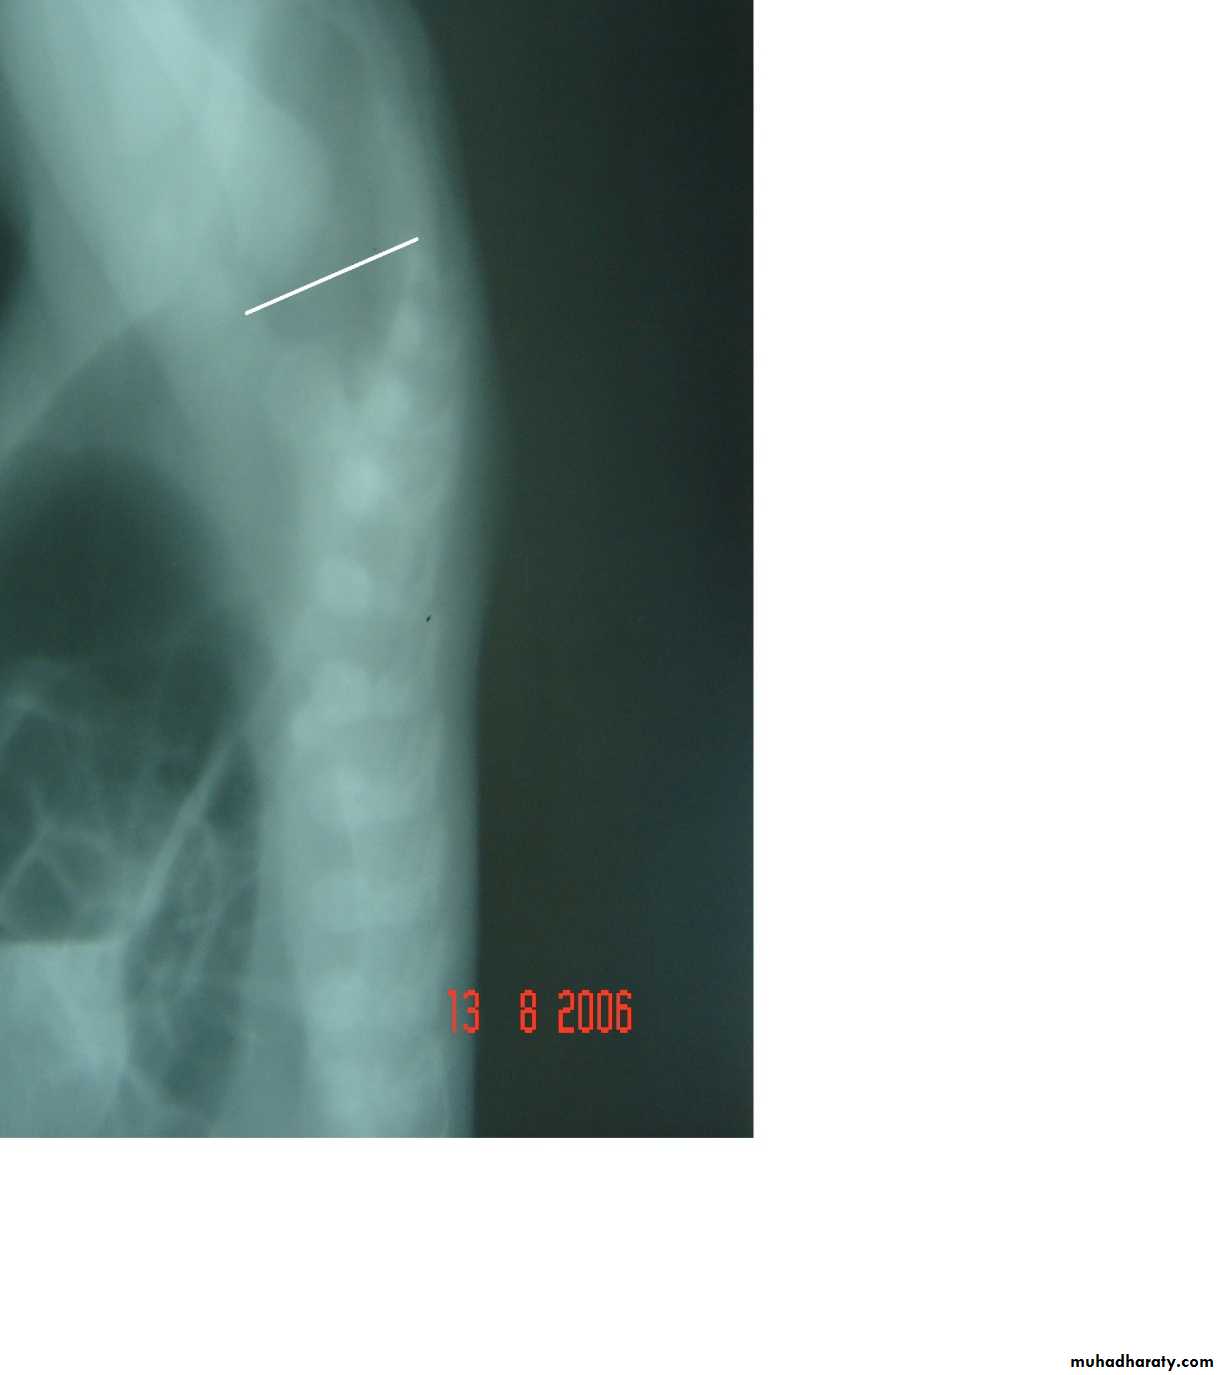

Subcostal incision